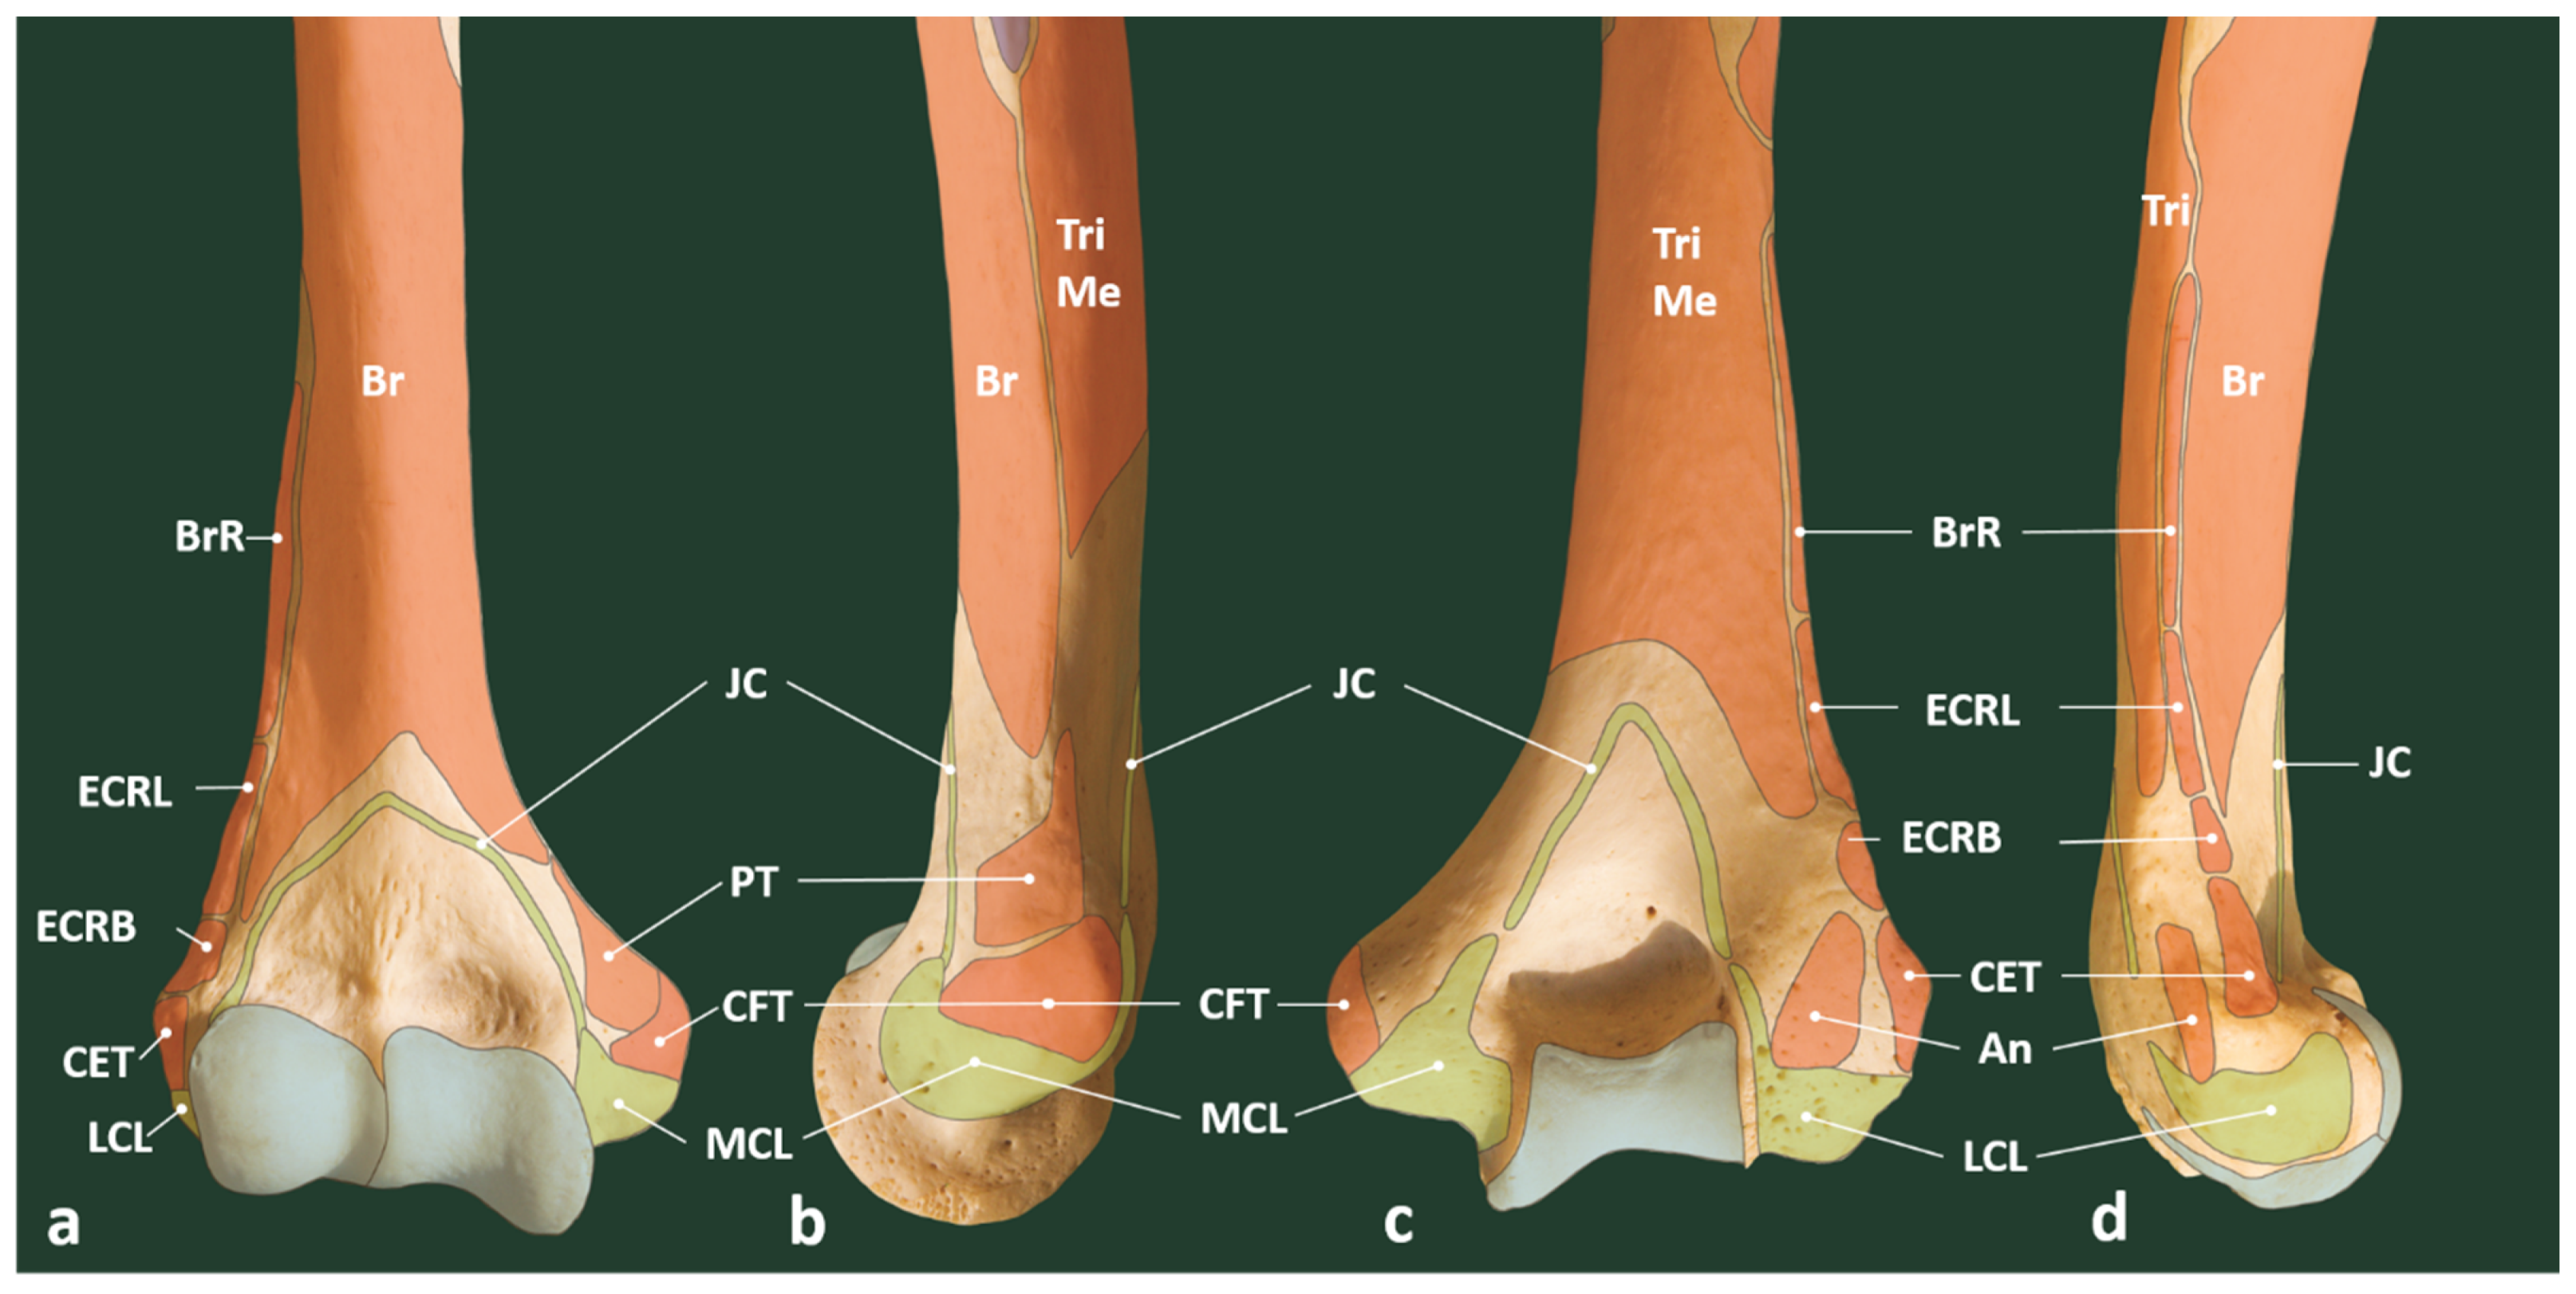

Figure 2.

Location of muscular and ligamentous attachments on distal humerus: (a) anterior, (b) medial, (c) posterior, and (d) lateral aspect of the right distal humerus. Light blue: articular surfaces. An: anconeus, Br: brachialis, BrR: brachioradialis muscle, CET: common extensor tendon, CFT: common flexor tendon, ECRB: extensor carpi radialis brevis muscle, ECRL: extensor carpi radialis longus muscle, JC: joint capsule, LCL: lateral collateral ligament, MCL: medial collateral ligament, PT: pronator teres, Tri: triceps brachii, TriMe: triceps brachii, medial head.